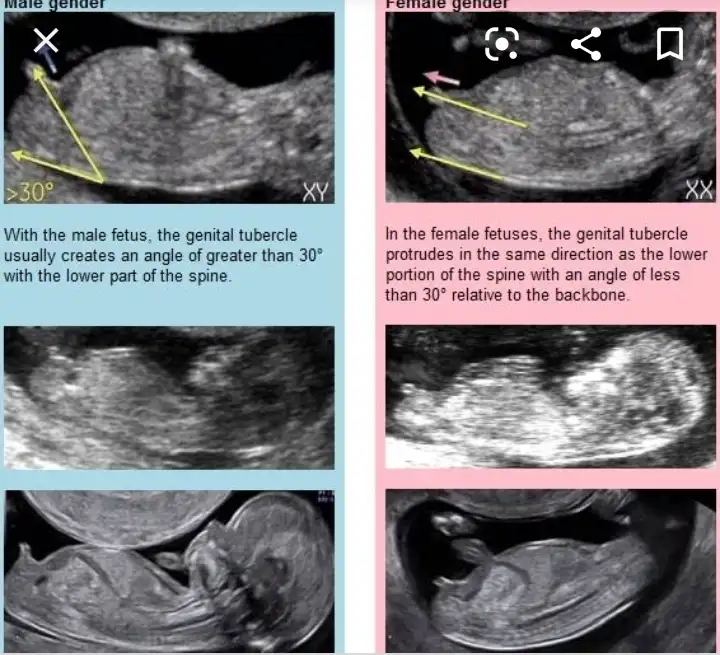

Nub teorisi ne göre özel bölge duzse kız yukarı bakıyorsa erkekValla nasıl anlıyonuz ya çıldırcam

Şu çıkıntı karşıya bakıyorsa kız yukarı doğruysa hafiften erkekk deniyorNasıl anlıyorsunuz kizlar